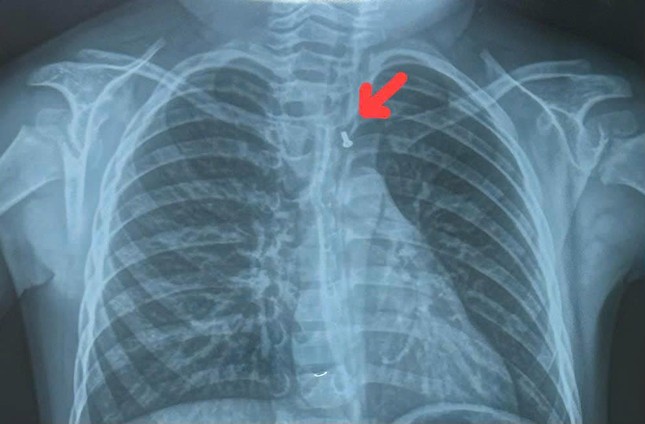

Cùng ngày, Bệnh viện Đa khoa Xuyên Á cho biết, tại đây cũng vừa tiếp nhận cấp cứu gắp dị vật là mảnh kim loại tròn, kích thước 17mm kẹt ở vùng hạ họng của bé trai T.P.T. (30 tháng tuổi, ngụ tại tỉnh Đồng Tháp). Trước đó, bệnh nhi đã ngậm mảnh kim loại trong miệng, khi chơi đùa đã vô thức nuốt dị vật, ngay lập tức trẻ rơi vào tình trạng khó thở, đau ở vùng họng, nôn ói.

Dị vật là mảnh kim loại gây tổn thương thực quản cho bé trai 30 tháng tuổi